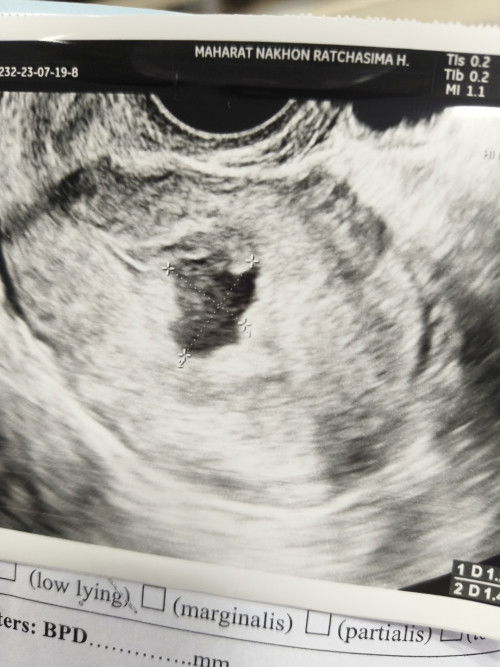

ถุงตั้งครรภ์ผิดรูปไม่เจอตัวอ่อน 8W5d

มีใครเป็นแบบเราบ้างไหมค่ะ ถุงตั้งครรภ์ไม่สวย ซาวด์ก็ไม่เจอน้อง ซางทั้งช่องคลอดและหน้าท้อง ครรภ์ 8W5d #เราเคลียดมากตอนนี้ ท้องนี้ท้องที่ 3 ท้องที่สองก็พึ่งแท้งไปครบปีพอดี ท้องนี้จะแท้งอีกไหมค่ะ